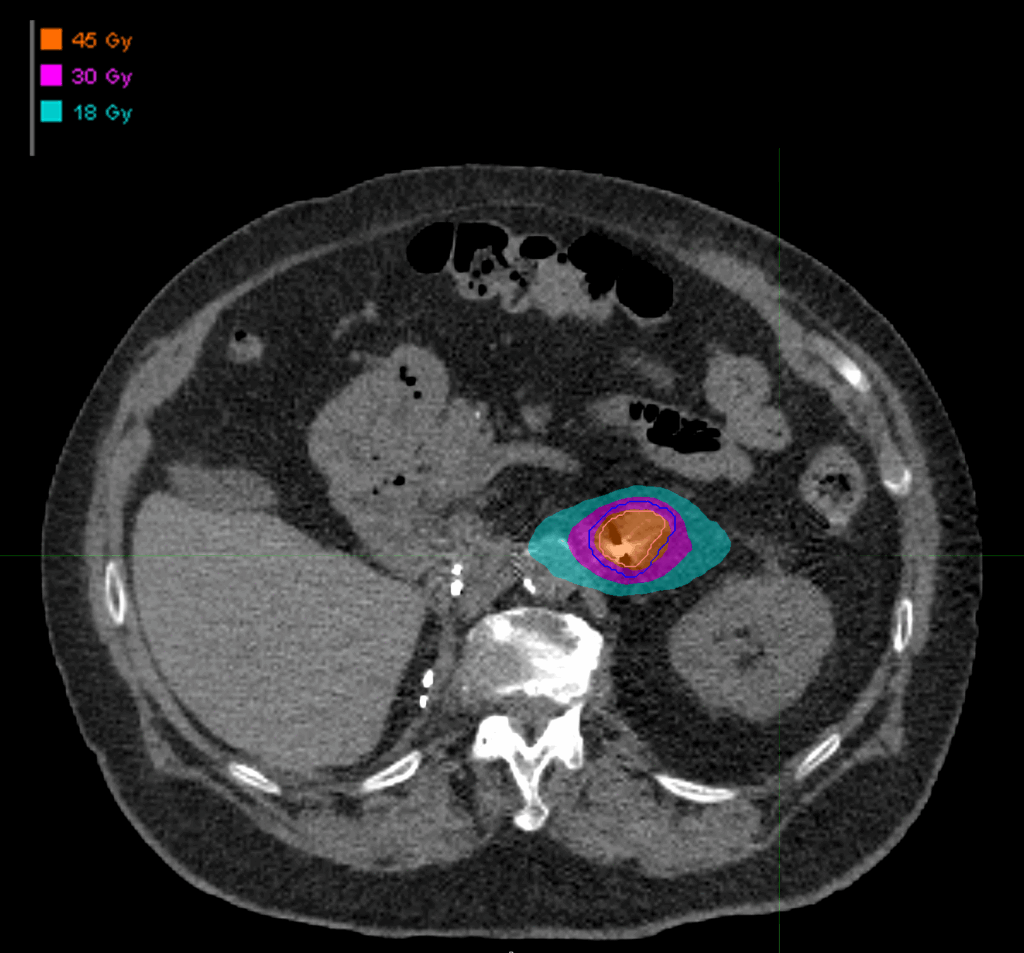

Treatment Plan Images

Dose Distributions

- Prescription to the 76.1% isodose line

- Max. dose 59.13 Gy